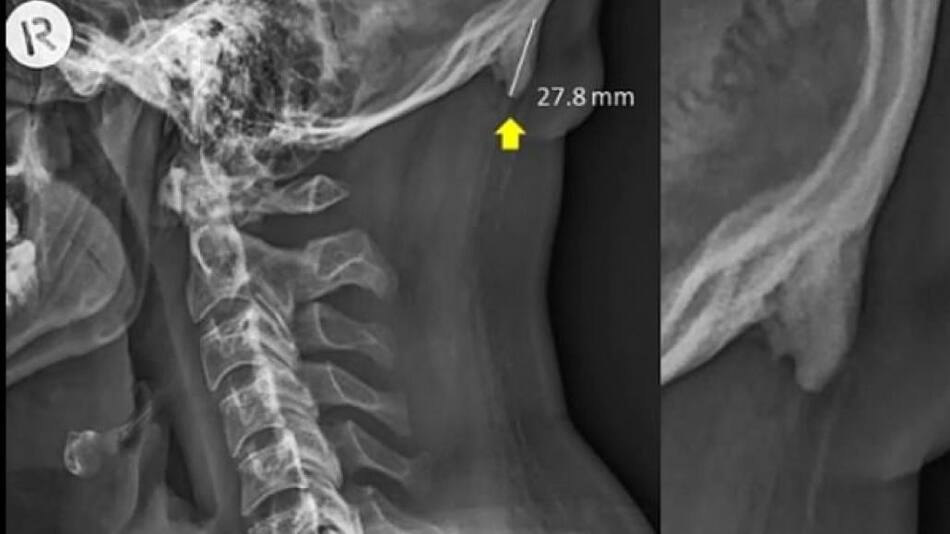

La estructura ósea trata de adaptarse para sostener mejor nuestra cabeza. La prueba está en las imágenes de rayos X publicadas por investigadores australianos. La cabeza de adulto promedio puede pesar alrededor de 5 kilogramos.

Los crecimientos llamados protuberancias occipitales externas agrandadas, se encuentran en la parte inferior del cráneo.